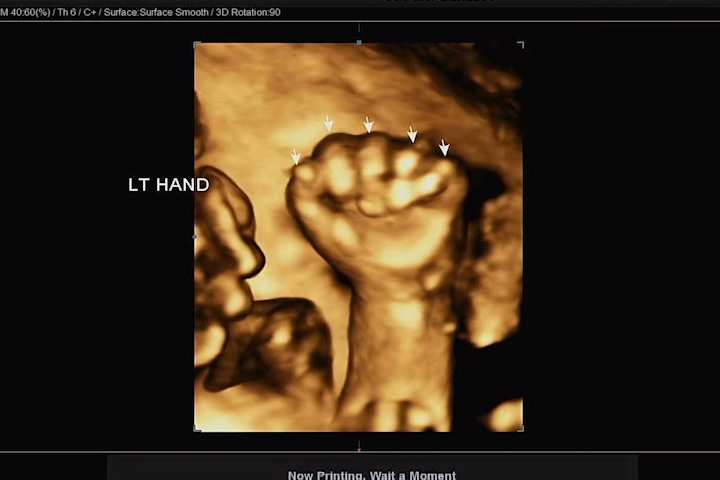

심박수와 손, 발 다섯개씩 무사히 잘 있고, 척추도 올곧게 있고 다행이다. 요 며칠 새 아내의 배를 만질 때 태동을 몇 번이고 느꼈던 지라, 점점 까꿍이가 우리에게 올 날이 머지않았음을 느끼고 있다. 우리 까꿍이 엄마 아빠가 너무너무 기다리고 보고 싶어 한다는 걸 알고 있을까!